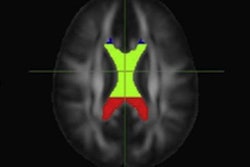

More specifically, the group with high blood pressure showed lower fractional anisotropy values in brain fibers in the anterior thalamus, affecting nonverbal skills; nerve fibers in the superior longitudinal fasciculus, which are involved with executive function and regulating emotions; and limbic system fibers of the cingulate gyrus, which are associated with attention tasks.

DTI-MRI illustrates the main tracts affected by hypertension. Reconstruction shows lower fractional anisotropy levels in regions including the anterior thalamic radiations, superior longitudinal fasciculus, and cingulate gyrus, resulting in significant deterioration in hypertensive patients. Image courtesy of Daniela Carnevale, PhD.And, if that wasn't enough, MRI scans also confirmed damage to the heart and kidneys among members of the high blood pressure group.